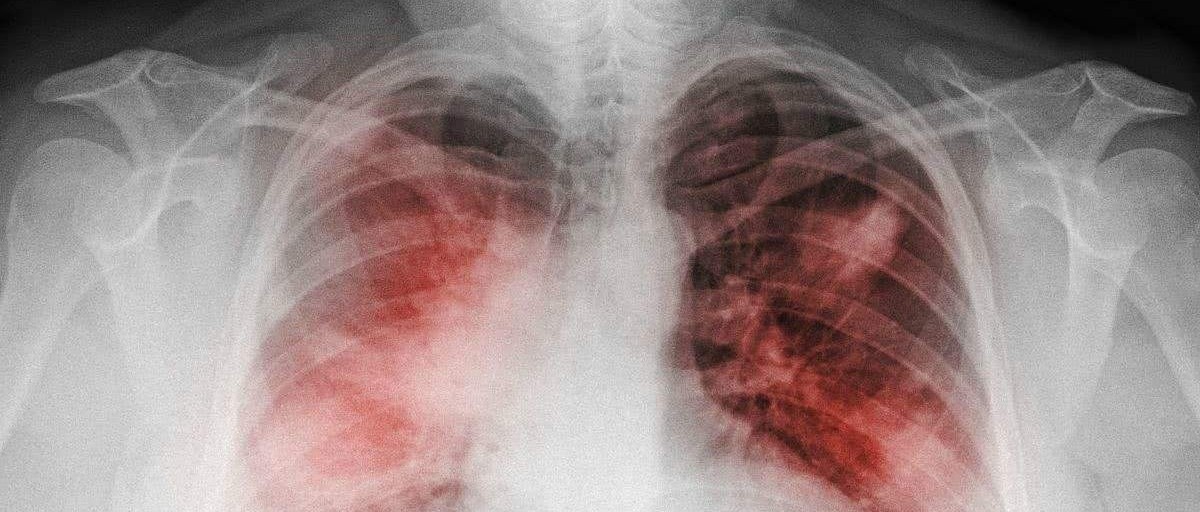

急诊常用评分(3)--临床肺部感染评分(CPIS)

临床肺部感染评分(CPIS)是一项综合了临床、影像学和微生物学标准等来评估感染严重程度,预测患者使用抗菌素时